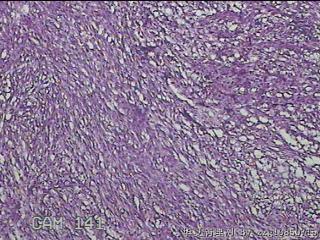

左肘部包块

性别

男

年龄

39

临床诊断

左肘部肿物:炎性脂肪瘤

一般病史

发现左肘部肿物1周。

标本名称

大体所见

灰白粉红色组织2x1.8x0.3㎝一团,表面结节状,光滑,切面灰白粉红色,质软。

图2